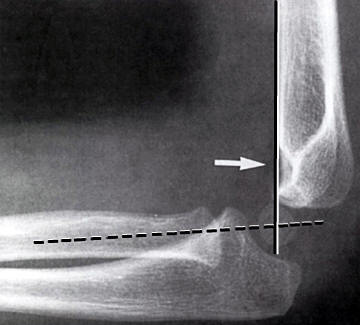

Dislokation: En linie langs forsiden af humerus går normalt igennem midterste

1/3 del af capitulum humeri. Hvis hele capitulum ligger bagved denne linje skal

der reponeres og osteosynteres i GA. Hos børn under 4 år tillades lidt større

dislokation.